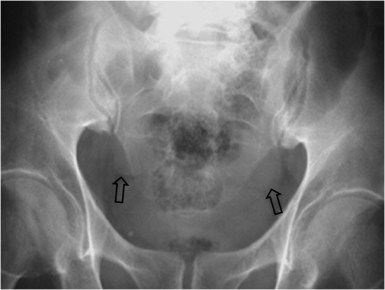

SIGNO DE LA CRESTA ILÍACA

Cuando existe ascitis, el líquido aumenta la densidad del peritoneo en la radiografía simple de abdomen, cuya interfase con la grasa properitoneal produce una línea vertical radiotransparente sobre la cresta ilíaca.

Corte de TC de pelvis con contraste oral e intravenoso que muestra abundante líquido libre abdominal. La presencia del líquido junto a la grasa properitoneal justifican la interfase –marcada con las flechas- en el signo de la cresta ilíaca.